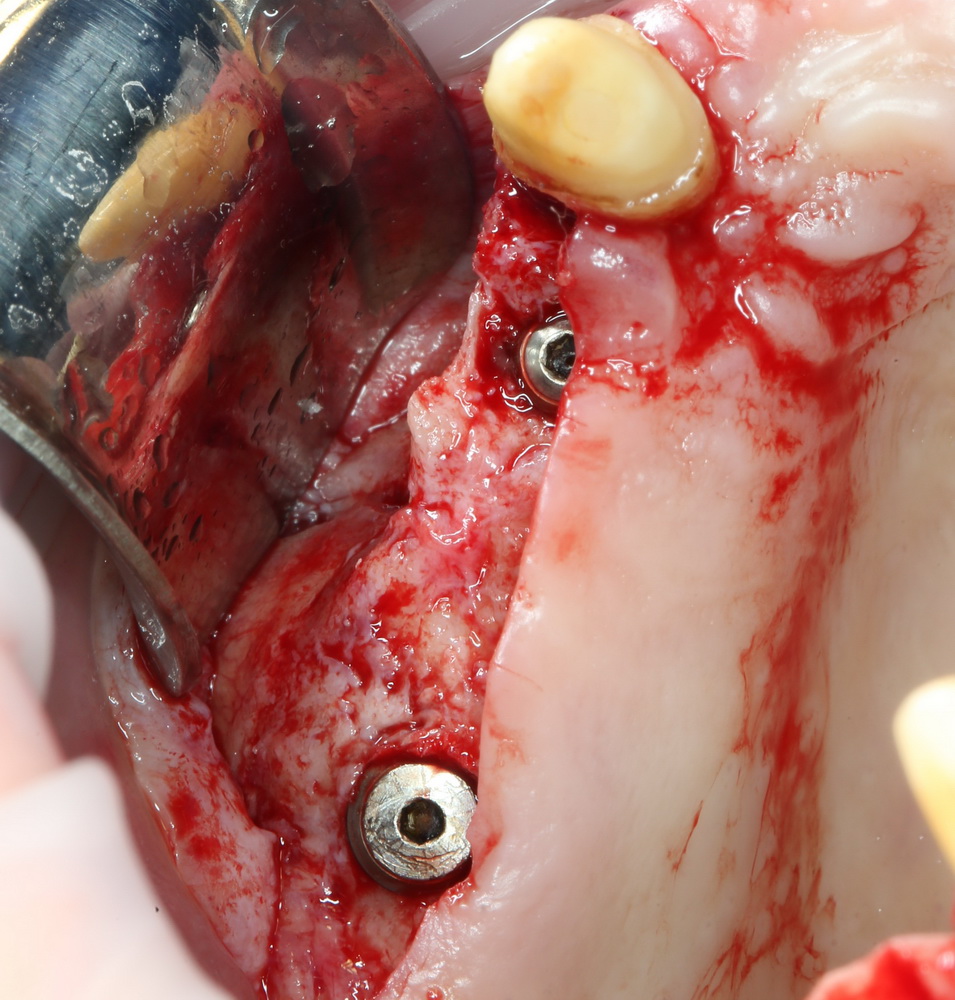

расставить импланты, по шесть штук на каждую челюсть. Разумеется, не все сразу, а постепенно:

А потом еще расставить формирователи десны на установленные импланты:

И удалили. Вместе с протезом. Через 15 минут после удаления Давид зафиксировал временный протез с опорой на импланты: